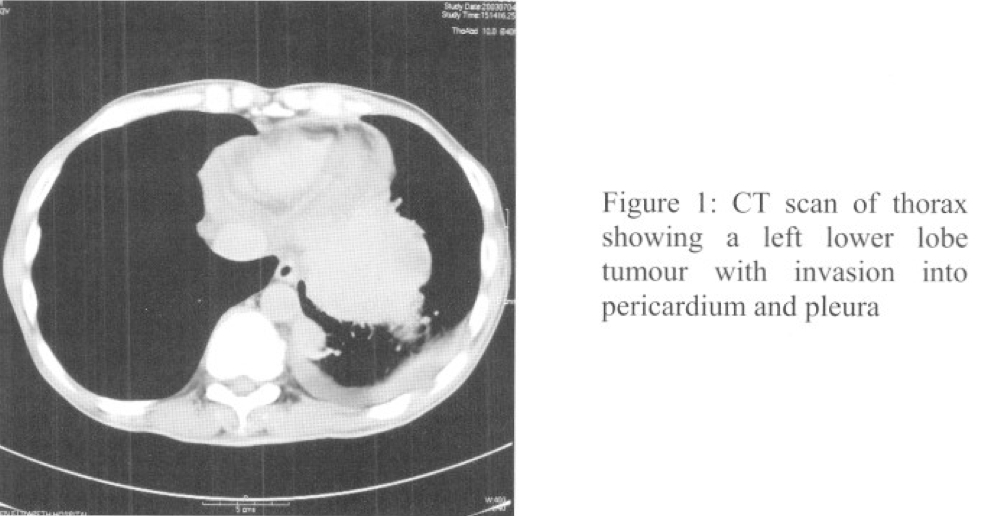

A 43-year-old male chronic smoker and drinker, was suffering from epilepsy and putting on dilantin and epilim since 1990. He complained of 3-month history of weight loss, malaise and anorexia. He was afebrile with stable vital sign on admission. Body weight was 47 kg (with height 175 cm) and there was no finger clubbing or palpable lymph node. On chest auscultation, breath sounds were decreased over left lower zone. Other examination was unremarkable. Complete blood picture showed mildly elevated WCC 9.3 units (Neu 6.3 Lym 1.3 Eos 0.1) with increased ESR 83 units. Renal and liver function tests were normal except hypoalbuminaemia (alb 24 units). Calcium and LDH level were within normal range. PO2 and PCO2 were 13 and 4.6 kPa (Room Air) respectively. Dilantin and epilim levels were below therapeutic range. Urine RBC and albumin were negative. Sputum AFB, culture and cytology were also negative. CXR (PA and left lateral) showed a left lower lobe shadow. CT thorax with contrast showed 2 tumour masses at left lower lobe with invasion into pericardium and pleura at lung base. Pericardial and pleural effusions were noted. There was also a 0.8 cm mediastinal lymph node at AP window regions (Figure 1). Echocardiogram showed moderate pericardial effusion at apex of the heart.